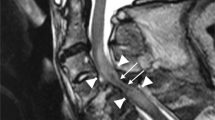

In the present study, the imaging data of 70 patients were collected and reviewed. For the other 18 patients, MRI data were not complete. No patient presented with a spinal fracture or dislocation on X-ray and CT images, although 67 patients had abnormal signals on T2WIs, which consisted of long T2 signals centering on the central canal of the spinal cord. The length of the long T2 signal was less than one vertebrae in two patients and more than one in 65. No patient had signs of significant hemorrhage on MRI (Fig. 3). Among these 67 patients, spinal cord edema most commonly involved the lower thoracic spine and lumbosacral medulla (Fig. 4). Of the 70 patients with imaging data, 45 had spinal cord atrophy, which was most commonly (40 patients) concentrated between T8 and the conus medullaris. Of these 45 patients, 30 (66.7%) developed atrophy within 90 days, including 4(8.9%) within 1 month, and 15 (33.3%) at more than 90 days. As to analysis of axial T2WIs, three patients had a BASIC score of 0, seven had a BASIC score of 1, 57 had a BASIC score of 2, three had a BASIC score of 3, and none had a BASIC score of 4 (Fig. 5).

A schematic diagram of BASIC scores is shown in the “Sketch Map” column. BASIC score of 0: no abnormality; BASIC score of 1: involvement of the gray matter only; BASIC score of 2: involvement of both the central gray matter and adjacent white matter; BASIC score of 3: total involvement of the spinal cord; BASIC score of 4: involvement of the whole spinal cord with hemorrhage. a A 5-year-old girl with an injury at T8 with no appreciable abnormal signals. b A 10-year-old girl with an injury at T6 with “butterfly-like” enhancement of the gray matter, which is a typical sign of spinal cord ischemia. c A “ring-like” change of a 6-year-old girl with an injury to T10 mostly involving the central gray matter with some involvement of the adjacent white, but not the peripheral white matter. d Involvement of the whole spinal cord of a 6-year-old girl with injury to T11.

Characteristics of ischemia could also be found on axial T2WIs in the present study. SCIs of seven patients had a BASIC score of 1 with a typical “snake-eye” sign or “butterfly-like” gray matter enhancement. Fifty-seven patients had a BASIC score of 2, which involved the central gray matter and adjacent white matter, but not the peripheral white matter. These changes are consistent with the characteristics of spinal cord ischemia [21, 22]. In support of this view, Thompson [23] summarized the phenomenon of central necrosis and the involvement of the adjacent white matter, but not the peripheral white matter, and proposed that the gray matter is the most susceptible to ischemia, followed by the adjacent white matter, while the peripheral white matter is least susceptible. A 2005 imaging study conducted by Ishizawa et al. [22] described “ring-like” changes caused by ischemia, as further confirmed by Wang et al. [24], which were closely related to the anatomy of the blood vessels supplying the spinal cord. In this scenario, the anterior spinal artery fed the sulcus artery to supply the gray matter, as well as the lateral and base of the posterior white matter, while the peripheral white matter was supplied by the pial and coronary arteries. The intermediate region between the central and peripheral areas is a watershed that is supplied by the end of the two systems.